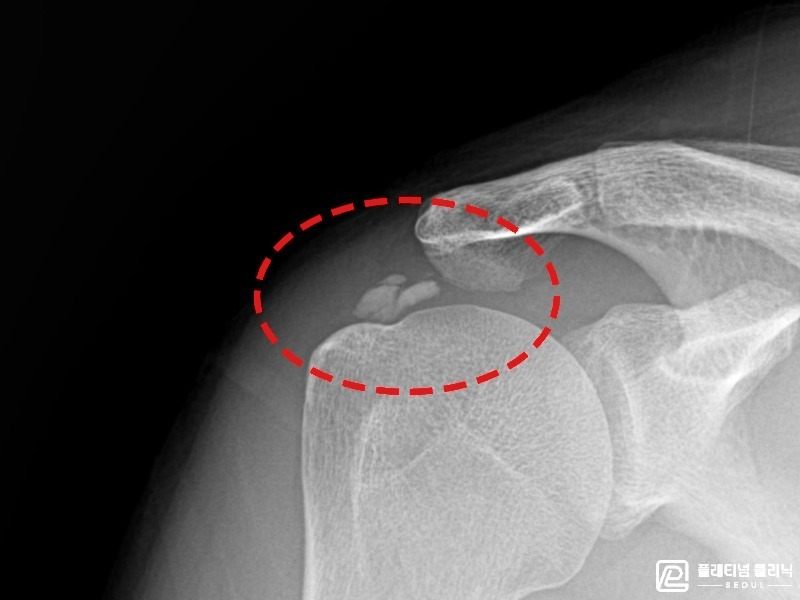

[촬영시기:21.09.27~21.10.07]

[석회분쇄흡입술] 우측 어깨의 야간 통증과 운동 제한으로 수개월간 고통받다 내원한 50세 남성 환자로, X-ray에서 극상근건 내 석회 침착이 확인되어 석회분쇄흡입술을 시행하였습니다.